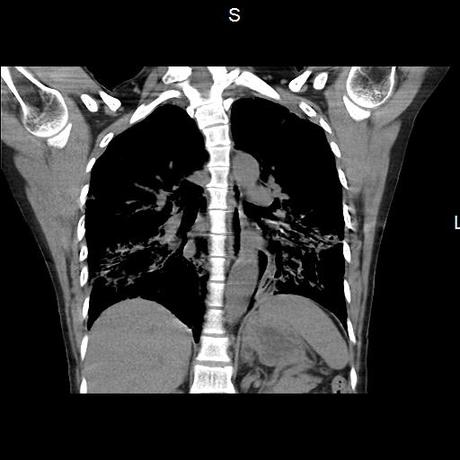

Se realiza volumen de tórax en fase simple, desde los opérculos torácicos hasta los hemidiafragmas, observándose:

El parénquima pulmonar con areas parcheadas difusas en vidrio despulido combinadas con otras areas hipodensas de baja atenuación debidas a atrapamiento aéreo y engrosamiento intersticial y zonas de fibrosis de predominio en lóbulos medios e inferiores de ambos pulmones.

- LOS HALLAZGOS PUEDEN ESTAR EN RELACIÓN A NEUMOPATIA INTERSTICIAL PROBABLE ETIOLOGIA HIPERSENSITIVA VS AUTOINMUNE/BACTERIANA/FUNGICA.